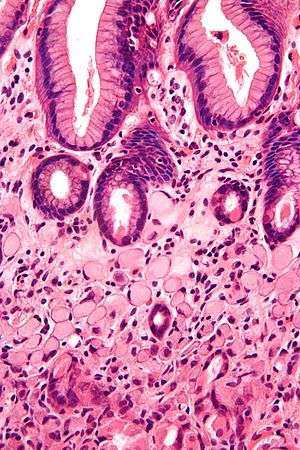

| A signet ring cell carcinoma of the stomach. Signet ring cells are seen in the lower half of the image. Gastric epithelium is seen in the upper half of the image. H&E stain. | |

SRCCs are named due to their resemblance to signet rings, which result from the formation of large vacuoles full of mucin that displace the nucleus to the cell's periphery.[16]